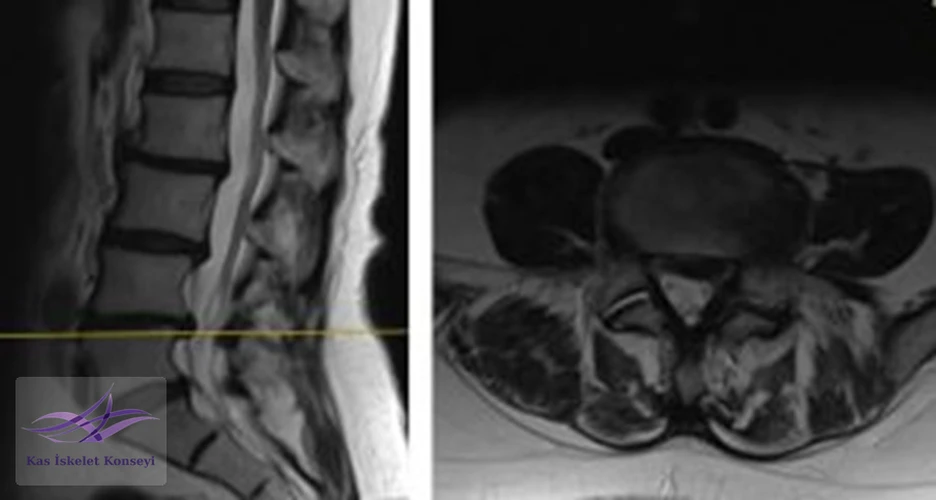

İncelemeler: Lomber MRG: L4-5 diskal bulging ve sol foraminal stenoz var. Kalça MRG istendi, iki yanlı trokanterik bursit rapor edildi.

Resim 1. Lomber MRG, L4-5 seviyesi median kesit.

Resim 3. Lomber MRG, L4-5 seviyesi sol paramedian kesit foramen stenozunu göstermekte.